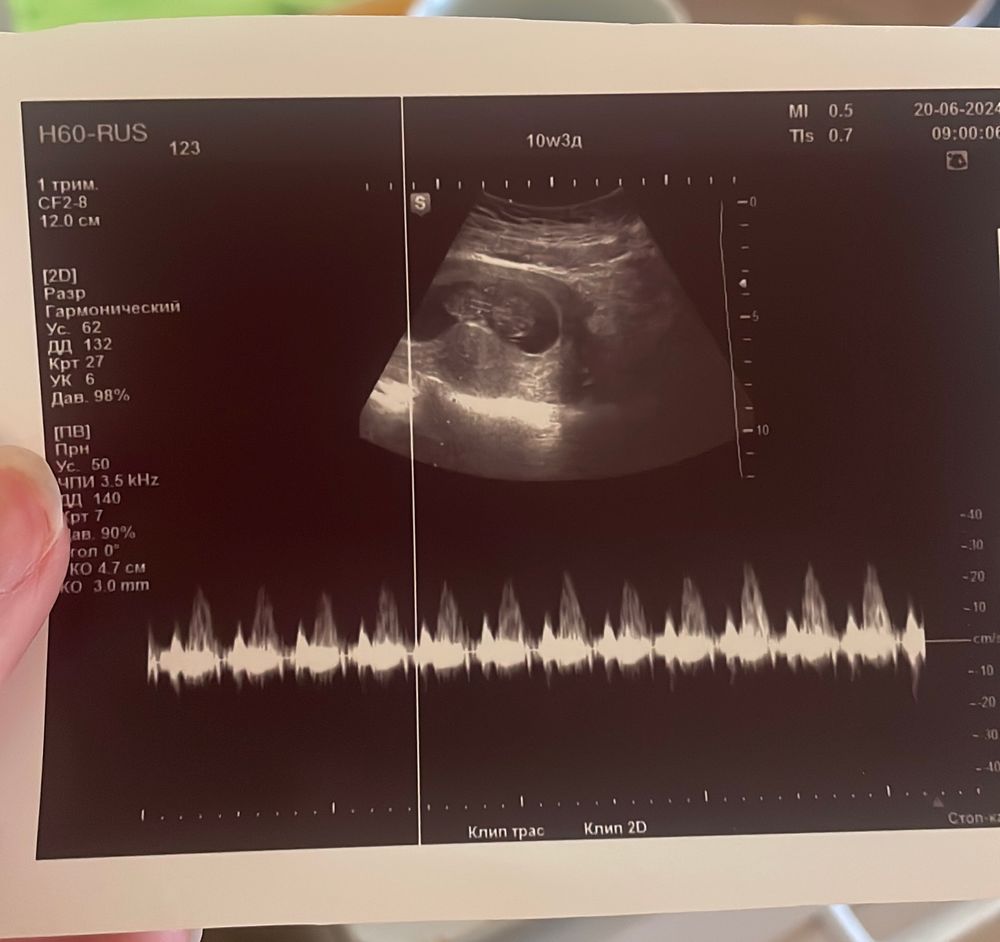

56 дпп или 10 неделя

Результаты УЗИВсе еще лежу в стационаре, неделя, надеялась, что после сегодняшнего узи отпустят домой, но как-то надежда тает, поставили тонус и гематома, но непонятно пока уменьшились она или наоборот

вот такое сплющенное ПЯ, а ребеночек такой активный 😍🥹